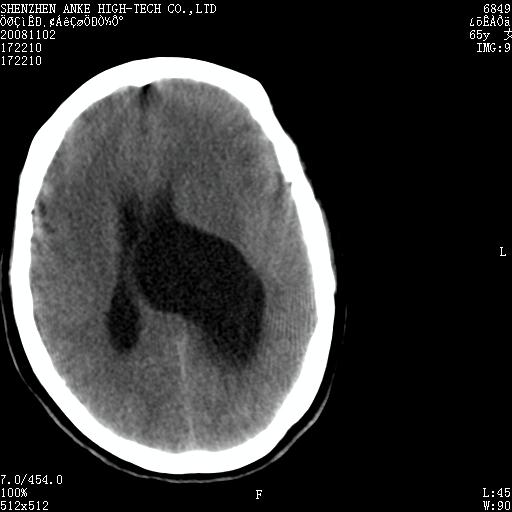

患者,女性,65岁,突发右侧肢体无力伴头痛,恶心、呕吐3小时.

比较典型的脑膜瘤

左侧脑外占位(脑膜瘤)压迫脑实质、脑室侧室孔所致。

1 左侧顶区圆形病灶,内可见钙化,考虑脑膜瘤,建议增强。2 左侧侧脑室病变,考虑神经上皮囊肿。

左顶脑外占位(脑膜瘤)压迫脑实质、脑室侧室孔所致。

1)左侧顶区脑膜瘤可能性大;建议必要时行进一步检查。2)左侧脑室积水。

左顶部脑膜瘤,左侧侧脑室蛛网膜囊肿,建议增强.

左侧脑外占位(脑膜瘤)压迫脑实质、脑室侧室孔所致积水。支持!